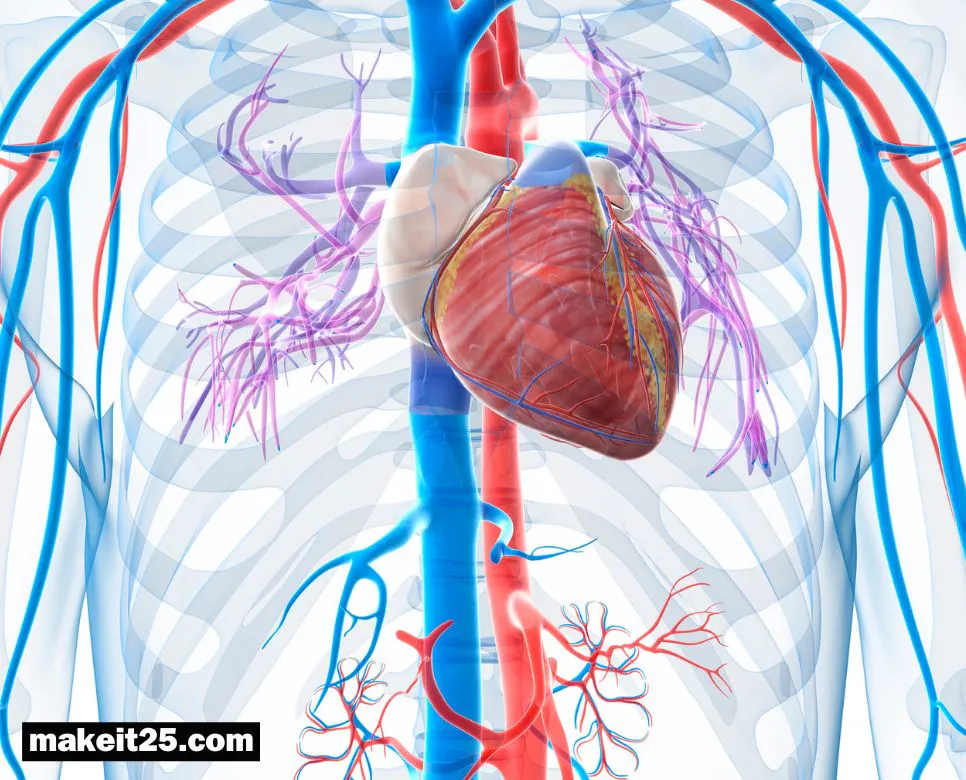

경정맥 손상은 목에 있는 큰 정맥이 손상되는 것을 말합니다. 심각한 출혈과 뇌졸중, 심장마비 등의 합병증을 유발할 수 있는 위험한 질환입니다. 경정맥 손상의 경우 응급 치료가 필요합니다. 혈관재건술은 손상된 경정맥을 복구하여 혈액순환을 회복시키는 수술입니다. 이 포스팅에서는 경정맥 손상과 혈관재건술에 대해 자세히 알아보겠습니다.

경정맥 손상이란 목에 있는 정맥이 손상되는 것을 말합니다. 경정맥은 머리와 목의 혈액을 심장으로 운반하는 큰 정맥으로, 뇌로 가는 혈액의 약 1/3을 담당하고 있습니다. 따라서 경정맥 손상은 심각한 출혈과 뇌졸중, 심장마비 등의 합병증을 유발할 수 있는 위험한 질환입니다.

혈관재건술이란 혈관이 손상되거나 막혀 혈액순환이 원활하지 않은 부위에 새로운 혈관을 만들어 혈액순환을 회복시키는 수술입니다. 혈관이 손상되거나 막힐 수 있는 원인은 크게 외상, 질병, 선천적 이상 등이 있습니다.

혈관재건술은 혈액순환이 원활하지 않아 발생하는 다양한 질환을 치료하는 데 중요한 역할을 하는 수술입니다.